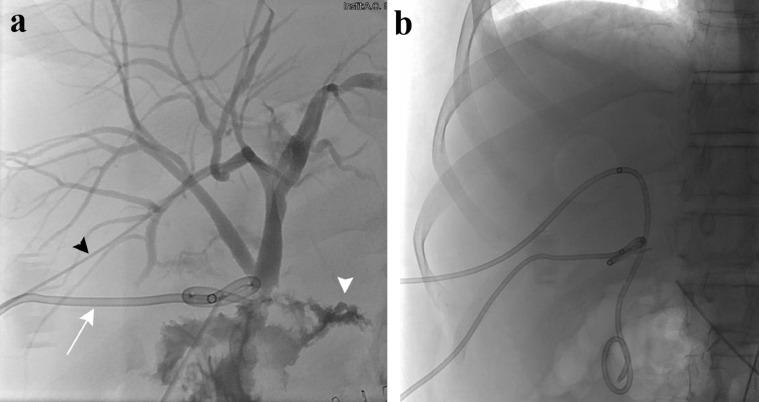

使用NBCA栓塞肝外胆管渗漏

Embolization of extrahepatic biliary leakage using NBCA.

Biliary fistula and bile leakage are complications that can occur during hepato-biliary or intestinal surgery and percutaneous biliary intervention. In some cases, spontaneous resolution is possible but more often re-intervention (surgical or percutaneous) is necessary. We present the case of a 45 y-o male patient who underwent duodenocefalopanreasectomy (Whipple procedure) with bilio-digestive anastomosis for adenoma of the duodenal papilla of Vater, complicated by the formation of a fistula through the bilio-digestive anastomosis. Conservative treatment with percutaneous biliary drainage was attempted in order to promote spontaneous resolution of the fistula. The persistence of the fistula brought the patient to treatment through interventional techniques. Sealing of the bilio-peritoneal fistula was obtained using N-butil-Cyanoacrylate .

摘要

胆瘘和胆汁渗漏是肝胆或肠道手术以及经皮胆道介入治疗过程中可能出现的并发症。在某些情况下,有可能自行缓解,但更常见的是需要再次干预(手术或经皮介入)。我们报告一例45岁男性患者,因十二指肠乳头腺瘤接受了十二指肠胰头切除术(惠普尔手术)并进行胆肠吻合术,术后并发通过胆肠吻合口形成瘘管。尝试采用经皮胆道引流进行保守治疗,以促进瘘管自行愈合。瘘管持续存在,导致患者通过介入技术进行治疗。使用N-丁基-氰基丙烯酸酯封闭了胆腹膜瘘。